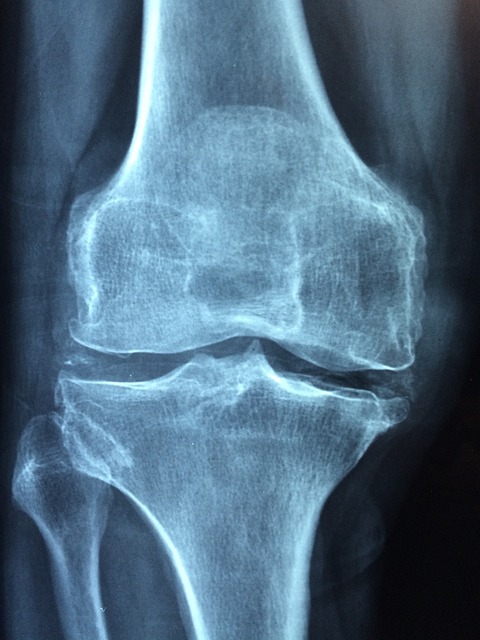

둘째, 노화로 인한 퇴행성 변화가 있다. 나이가 들수록 연골은 마모되고 탄력을 잃는다. 특히 50대 이상에서 퇴행성 관절염과 연관되어 연골 손상이 빈번하게 나타난다.

무릎 연골 손상의 치료는 상태에 따라 달라진다

무릎 연골 손상의 치료는 손상 정도와 환자의 상태에 따라 비수술적 치료부터 수술적 치료까지 다양하게 적용된다.

보존적 치료에도 효과가 없거나 연골이 광범위하게 손상된 경우, 관절내시경을 통한 연골 절제술 또는 봉합술이 시행된다. 젊은 환자의 경우에는 자가 연골을 채취하여 손상 부위에 이식하는 연골 이식술도 고려된다. 퇴행성 손상이 심해 일상생활이 어려울 경우에는 인공관절 수술이 최종 선택이 된다.